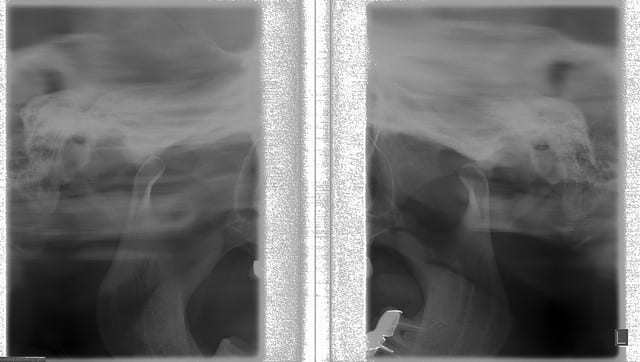

Les radios sont extraordinaires !!!! Quel beau jouet ,ça fait envie.

D'accord avec Marc: la pano est magnifique !